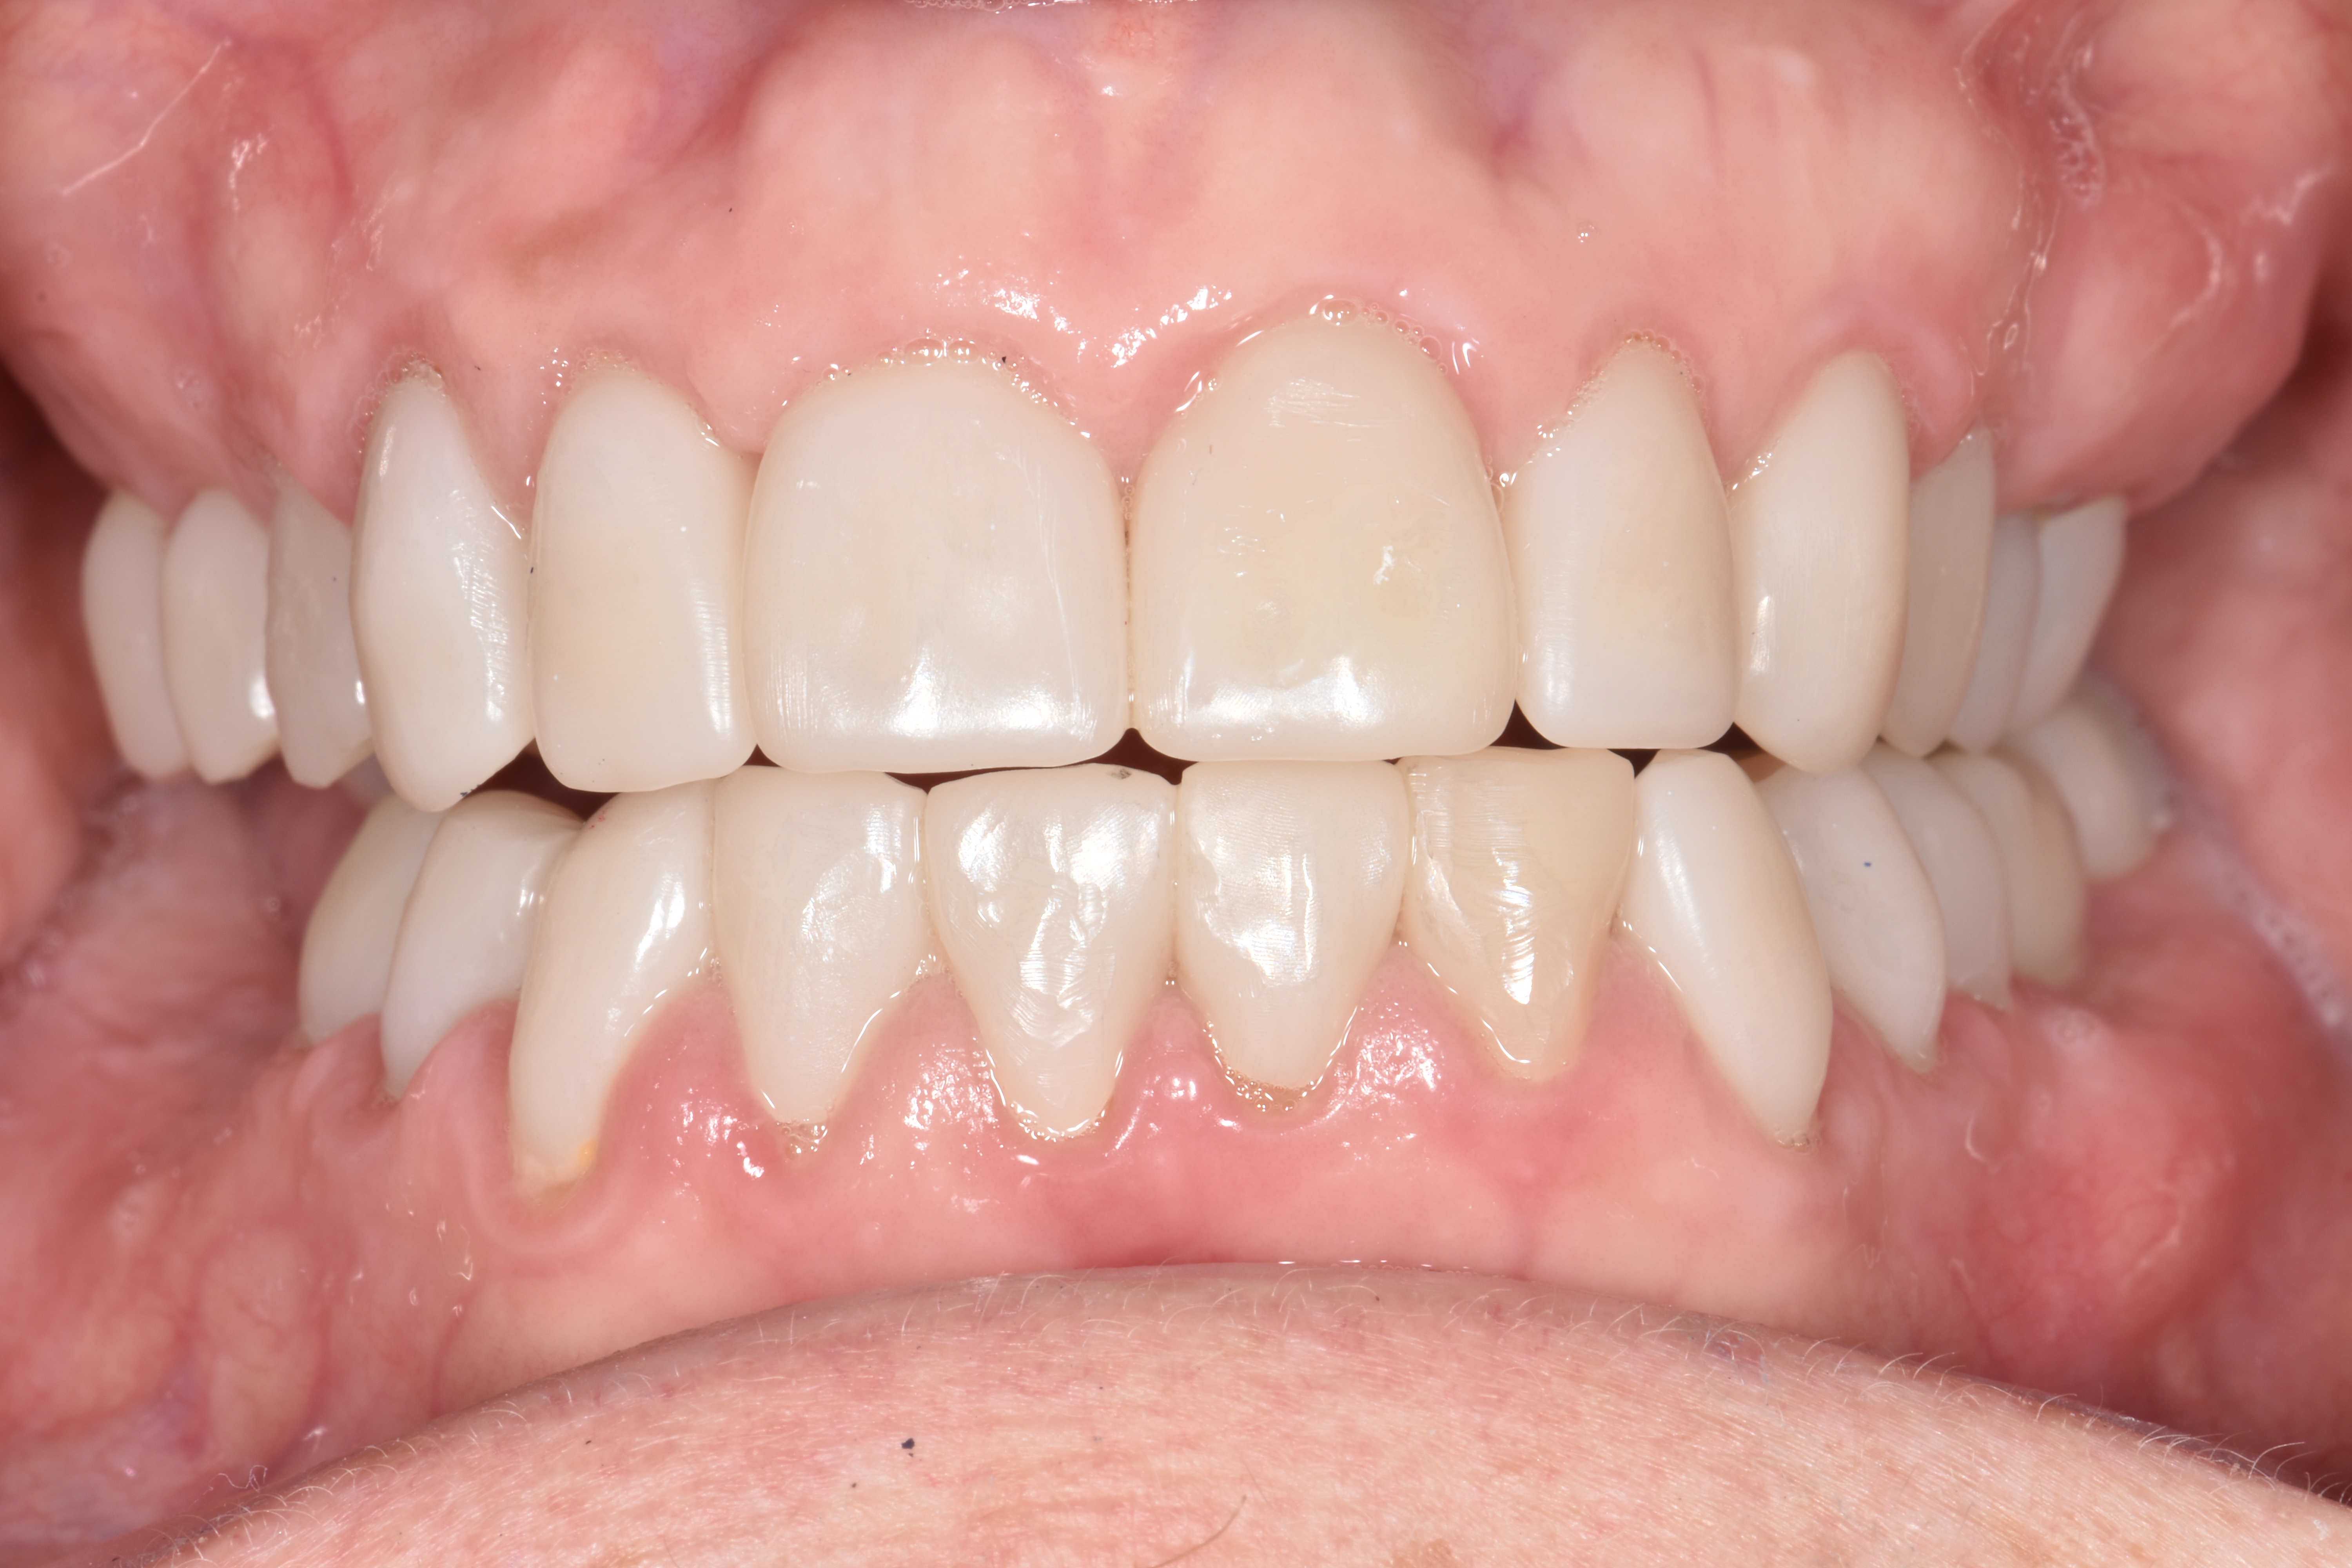

At a clinic treating patients in an underserved population, a 54-year-old female patient presented requesting extraction of all of her teeth and fabrication of dentures for her long-term restorations. The patient had a history of breast cancer, which had been treated with chemotherapy. She believed that full dentures would be an appropriate treatment option for her, owing to the poor state of her oral health and dentition and because she had limited financial resources and did not think that she could afford restoration of her teeth. The patient reported that she had experienced depression and alcohol abuse because of her cancer diagnosis, and that she had neglected her dental care during the course of her cancer treatment, resulting in generalized moderate-to-severe caries with moderate wear due to bruxism (Figure 1 through Figure 5). She also presented with significant staining of her remaining dentition due to the alcohol abuse.

After the restorations were milled, they were sintered and polished for final effect. It was decided that these restorations should not be glazed to avoid the added abrasivity that accompanies this finish to the restoration.22 The patient was then scheduled for temporary crown removal. The final crowns were fitted on the prepared teeth, and the contacts adjusted. The patient reported that she was pleased with the feel and esthetics of the restorations, and the restorations were cemented (Figure 14 through Figure 19).

Fig. 2

Fig. 3